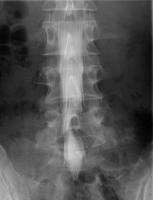

全脊椎撮影

脊椎全体の配列を観察する検査です。

自然位で寝た状態から、体を左右に曲げた側屈位や、腕と脚を引っ張った伸展矯正位、背中を反らせた最大後屈位などを撮影します。

EOS検査の立位荷重位と比較することが可能です。